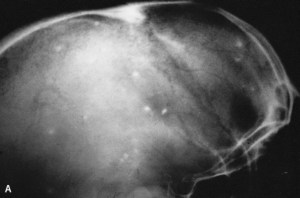

Plain radiographs of muscle may detect oval or linear calcified lesions (4-10 X 2-5 mm). The lesions are usually multiple, sometimes in the hundreds, and the long axis of the cysts are nearly always in the plane of the surrounding muscle fibers.

Plain skull films may demonstrate calcified cysticercosis.